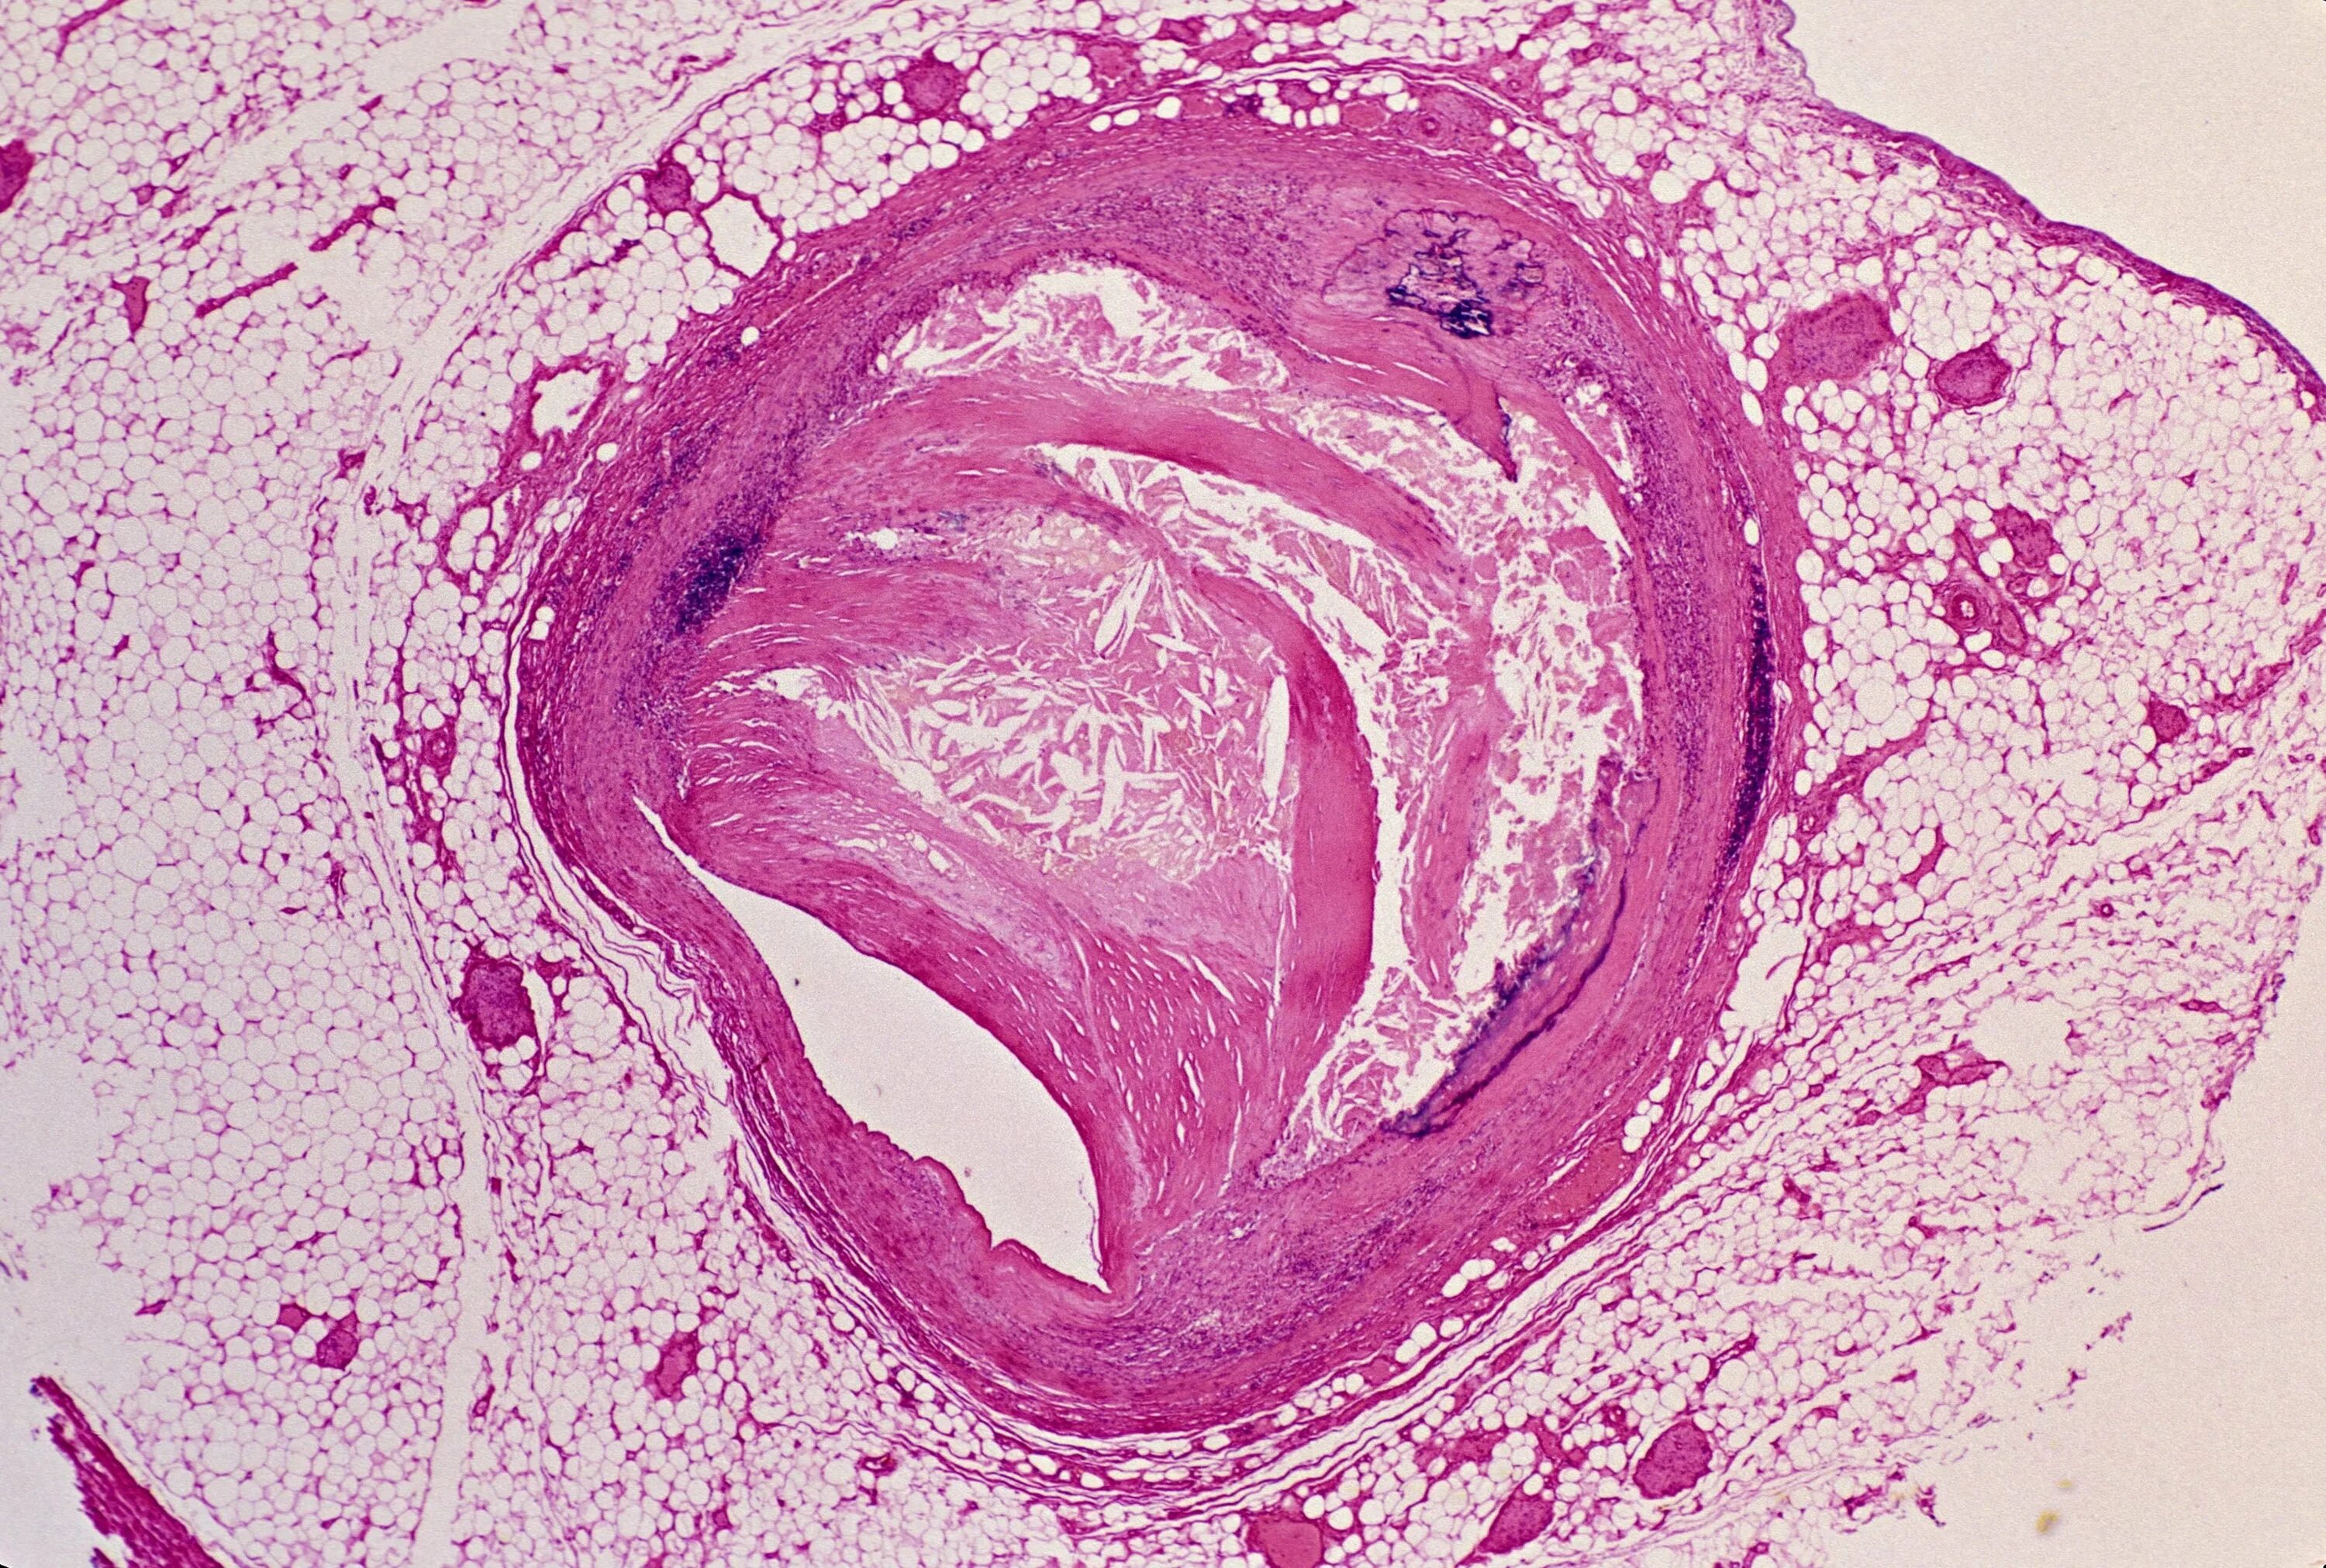

Атеросклероз 2025